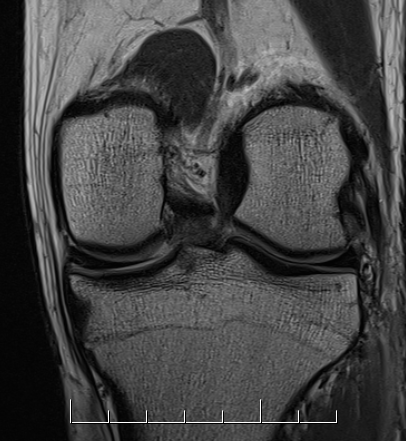

Coronal MRI of left knee demonstrating proximal MCL tear, with sagittal demonstrating complete disruption of ACL / PCL

Coronal MRI of left knee demonstrating femoral avulsion of popliteus

Coronal MRI with normal femoral insertion of LCL and popliteus

Coronal MRI of same patient demonstrating distal LCL avulsion from fibula